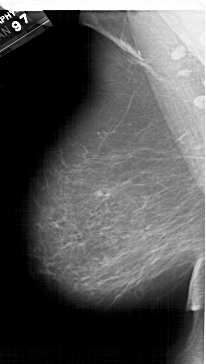

A_1615_1.RIGHT_MLO

RIGHT_MLO LINES 6406 PIXELS_PER_LINE 3931 BITS_PER_PIXEL 12 RESOLUTION 43.5 OVERLAY

FILE: A_1615_1.RIGHT_MLO.OVERLAY

TOTAL_ABNORMALITIES 1

ABNORMALITY 1

LESION_TYPE MASS SHAPE LOBULATED MARGINS CIRCUMSCRIBED

ASSESSMENT 4

SUBTLETY 5

PATHOLOGY BENIGN